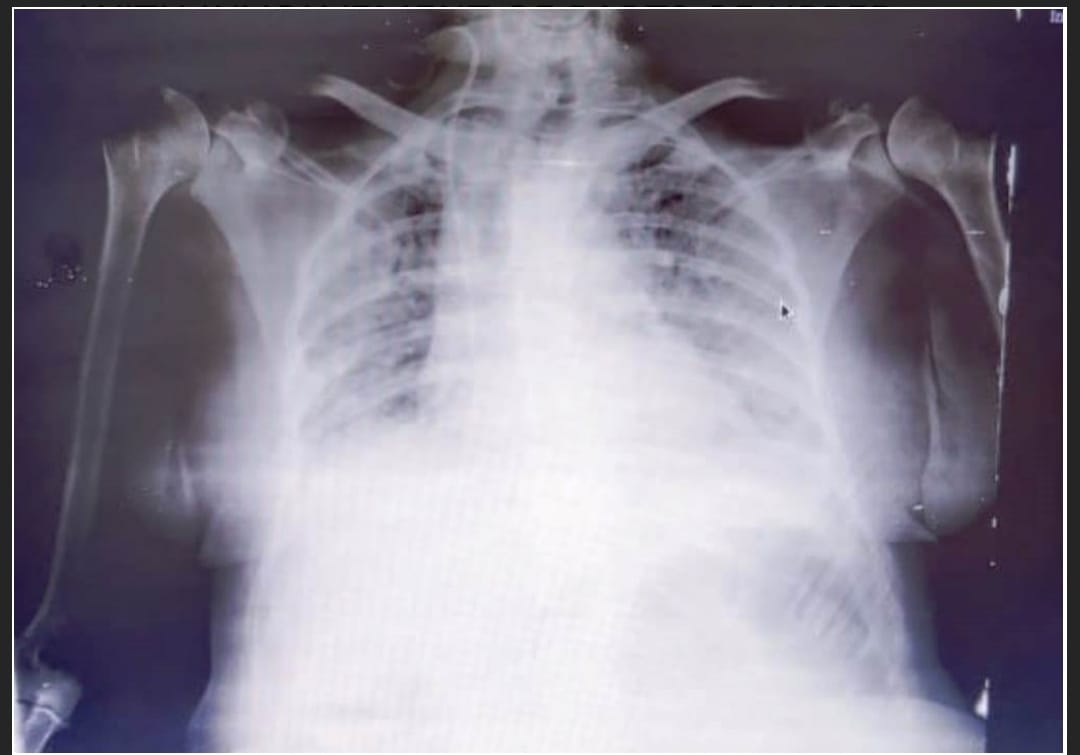

RADIOLOGICAL FINDINGS

Out of 15 patients, 8 had lung involvement on CXR PA. Out of these 8, HRCT chest was done in 6 patients of which 4 had bilateral lower lobe consolidation with CORAD 5, CTSS >15/40.

[FIGURE1]

CXR PA AND HRCT CHEST PLAIN OF PATIENT NO 8 WITH EXTENSIVE B/L LOWER LOBE CONSOLIDATION WITH INVOLVEMENT OF PARTS OF UPPER LOBES.

CXR PA OF PATIENT NO 14 SHOWING B/L 6 ZONE INVOLVEMENT

Out of 15 patients, 8(54%) had severe pneumonia and were provided with o2 supply. 6 by plain o2 masks, 1 by NIV and 1 by mechanical ventilation. These 8 showed lung involvement on CXR PA. Out of these we were able to do HRCT CHEST PLAIN of 6 patients, which showed bilateral lower lobe consolidation with CORAD 5, CTSS ranging from 18/40 to 28/40.